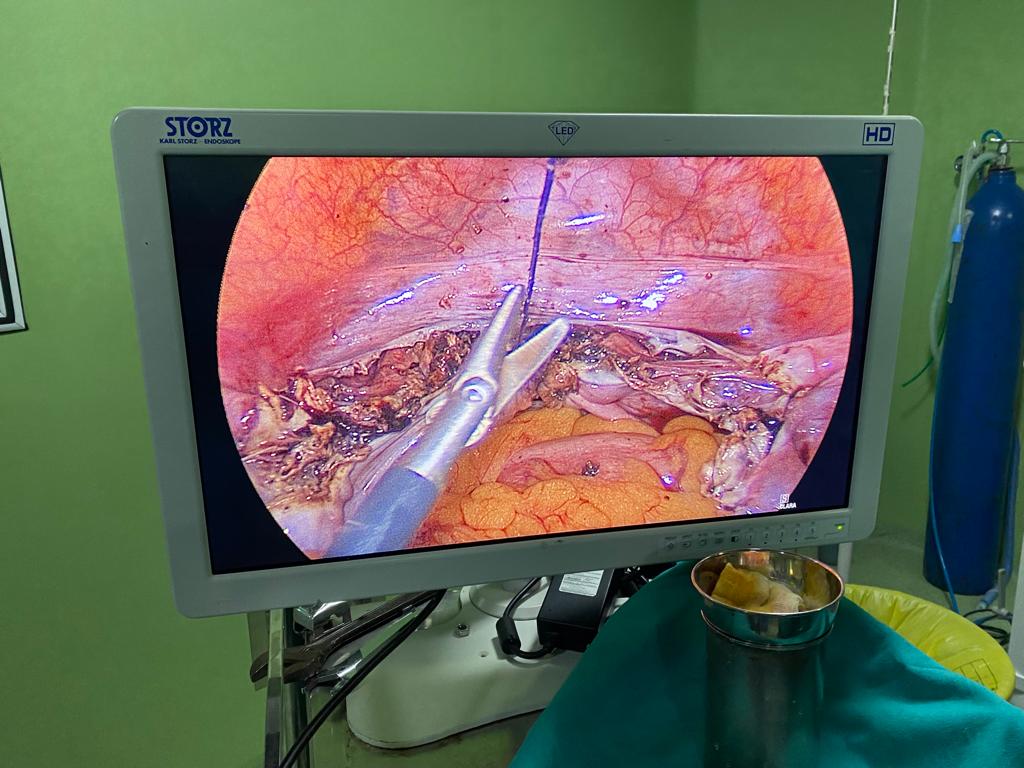

Difficult retrocecal appendix completely done laparoscopically